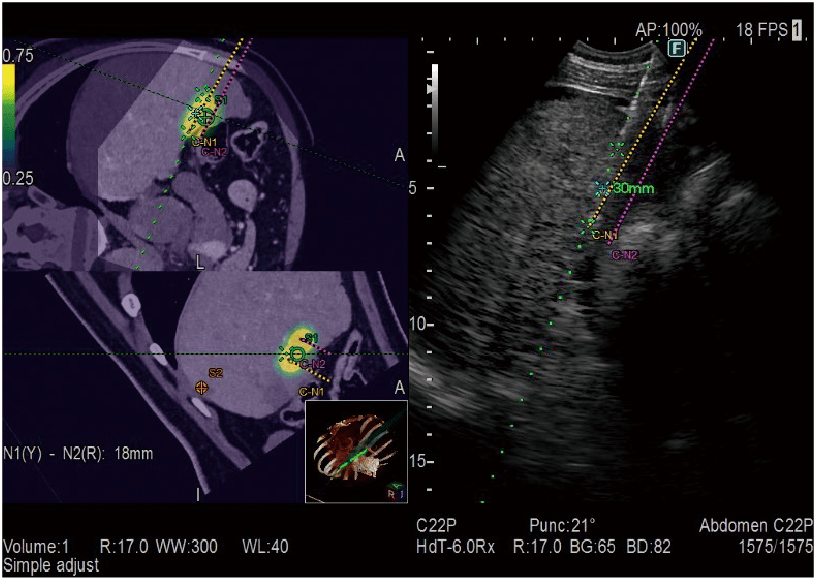

Real-time Virtual Sonography (RVS)

BT/MRG/PET-BT/Ultrason hacim verilerinden oluşturulan MPR görüntüleri, gerçek zamanlı ultrason görüntüleme ile senkronize edilebilir. Karın, Göğüs, prostat ponksiyonunda navigasyon vb. gibi çok çeşitli klinik alanlarda uygulanır.

3 Boyutlu Sim-Navigatör / E-alan Simülatörü

Real-time Virtual Sonography (RVS) ile hedefe yönelim sırasında tek veya birden fazla iğne yolunun simülasyonunu sağlar. İşaretlenen hedef ve iğne yolları arasındaki konumsal ilişki, 3 boyutlu vücut işareti ve C düzlem ekranı kullanılarak gerçek zamanlı olarak değerlendirilebilir. Elektrikli Alan Simülatörü, elektrotların belirtilen konumundan gelen elektrikli alanı (E-alan), RFA tedavisi sırasında BT görüntüsünün üzerine bindirir. E-alanının simülasyonu, etkili bir iğne yolunun göz önünde bulundurulmasını sağlar.